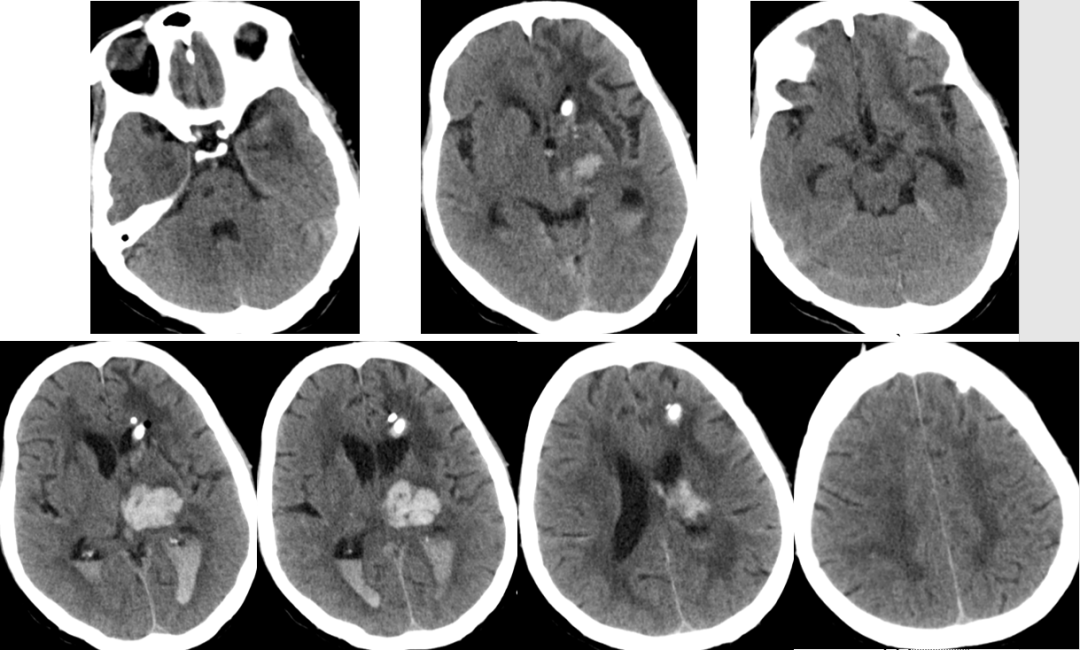

2014-11-18 0am CT

2014-11-18 10am CT

2014-11-19 CT

2014-11-20 CT

2014-11-24 CT

2014-11-18 CT